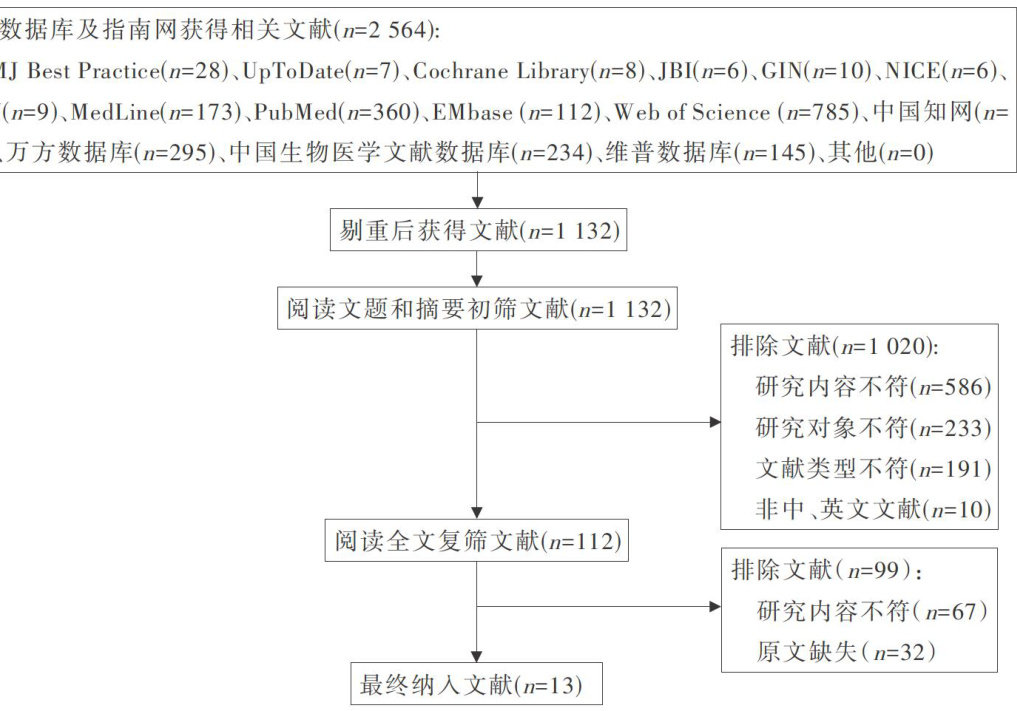

科研论著 | 不同浓度盐水鼻腔冲洗对慢性鼻窦炎内镜术后治疗有效性的网状Meta分析

科研论著 | 不同浓度盐水鼻腔冲洗对慢性鼻窦炎内镜术后治疗有效性的网状Meta分析